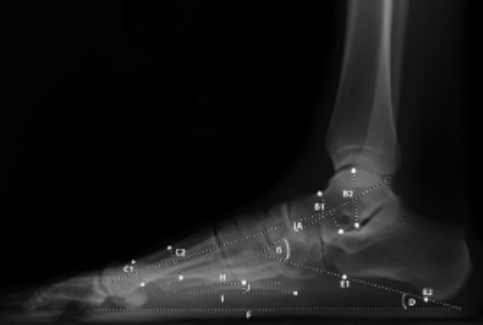

19 前后足—侧位距骨第一跖骨角

—侧位距骨第一跖骨角lateral talo-first metatarsal angle,meary‘s angle:侧位X线片上距骨轴线和第一跖骨轴线的夹角。反映前足和后足的对线关系,常用来评价足内侧足弓畸形,其交点可用来确定中足塌陷的部位。

正常范围:±4°(交于跖侧为正)。应用广泛。

4~15°轻度平足

15~30°中度平足

>30°重度平足